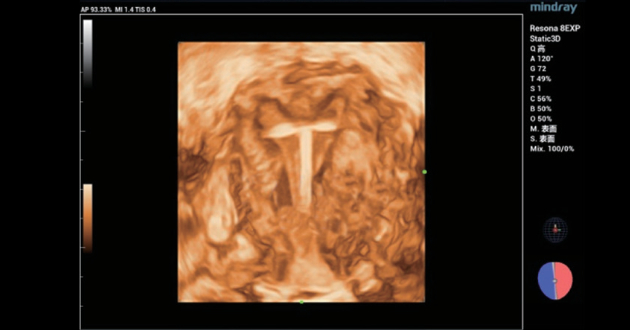

??1 ?? ??? ?? IUD ?? ??

4? ? IUD???? ?? 38? ??? ?? ??? ?? ??????, 2D ????? IUD? ??? ?? ??? ???????. 3D ???? ??? ?? ??? ??? ???????.(?? 1, ?? 2). 2D ???? ??? ?? ???? ???? ?? ? ??? ???? ?????.